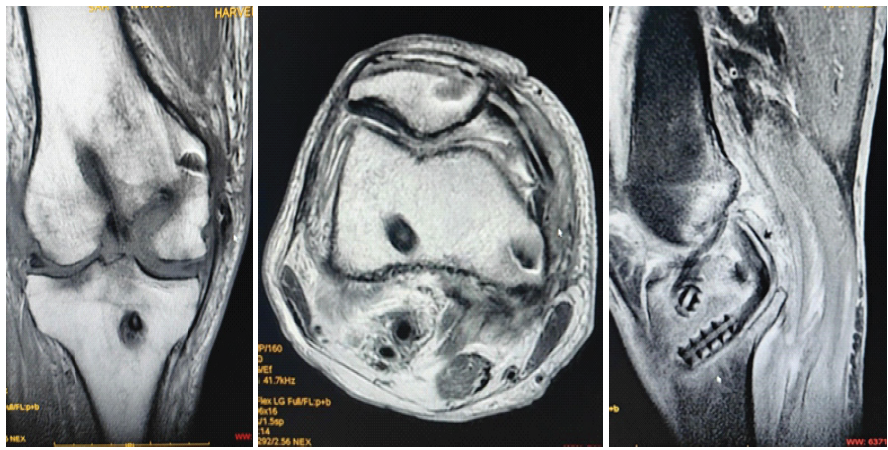

Radiographs at 3 months confirmed maintained joint alignment and stable fixation. Magnetic resonance imaging demonstrated intact reconstructed ACL, PCL, MCL, and MPFL grafts with satisfactory graft integration (Fig. 10).

Figure 10: Three-month post-operative magnetic resonance imaging showing reconstructed anterior cruciate ligament and posterior cruciate ligament, reconstructed medial patellofemoral ligament, and reconstructed medial collateral ligament.